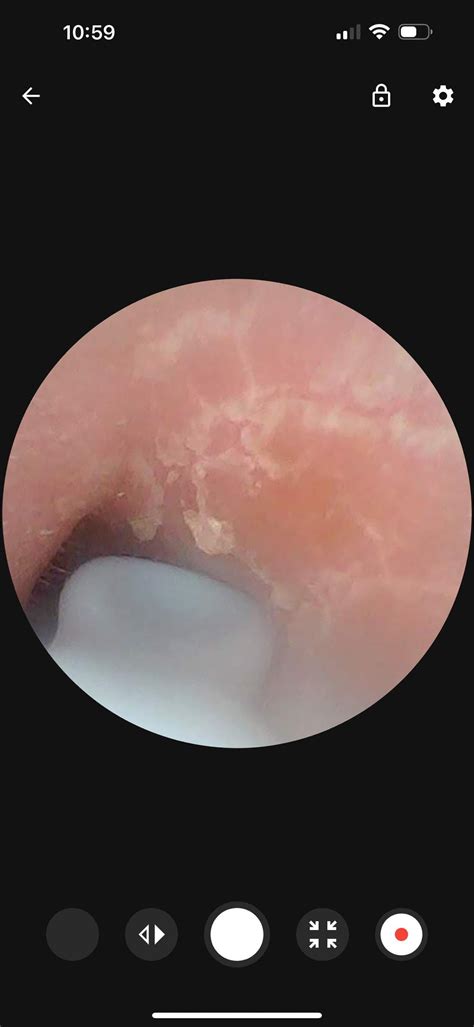

Dealing with psoriasis in ears canal can be an incredibly frustrating and uncomfortable experience. Unlike psoriasis on visible areas of the body, such as the elbows or knees, ear psoriasis is hidden deep within a sensitive, hard-to-reach area, making it difficult to treat and manage. This chronic autoimmune condition occurs when skin cells regenerate too quickly, leading to the buildup of silvery-white scales and itchy, red patches. When this occurs inside or around the ear canal, it often results in persistent itching, localized pain, and sometimes even temporary hearing issues due to the accumulation of skin debris.

• Scaling and Flaking: Dry, silvery-white skin shedding inside the ear.

• Redness and Inflammation: Affected areas of the ear canal may appear angry and inflamed.

• Sensation of Blockage: Excess skin buildup can physically block the canal, causing muffled hearing.